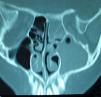

A la exploración presentaba dolor a la palpación sinusal maxilar y etmoidal izquierda, sin eritema de la piel, con movilidad ocular y agudeza visual normales. Se solicitó valoración al servicio de ORL que realizó una endoscopia nasal en la que se objetivó drenaje purulento espeso abundante por ostium maxilar izquierdo. Dado lo prolongado de la clínica con la exacerbación actual, los hallazgos exploratorios y la falta de respuesta a los tratamientos pautados, se solicita una TC de fosas y senos paranasales, en la que se observa una pansinusitis izquierda con ocupación completa del seno maxilar, complejo osteomeatal, celdillas etmoidales, seno frontal y esfenoidal izquierdos, con ocupación completa también del meato medio y superior izquierdos (fig. 1). Dentro del seno maxilar izquierdo se apreciaban imágenes de distintas radiodensidades (fig. 2).

La TC es la mejor prueba de imagen ya que permite observar la opacificación total o subtotal del seno afectado, en ocasiones con imágenes de esclerosis ósea de las paredes sinusales, objetivándose en el interior del seno diferentes radiodensidades, que corresponden a microcalcificaciones o hifas densas. Se debe recurrir a la RM si existe sospecha de invasión craneal o intraorbitaria10.